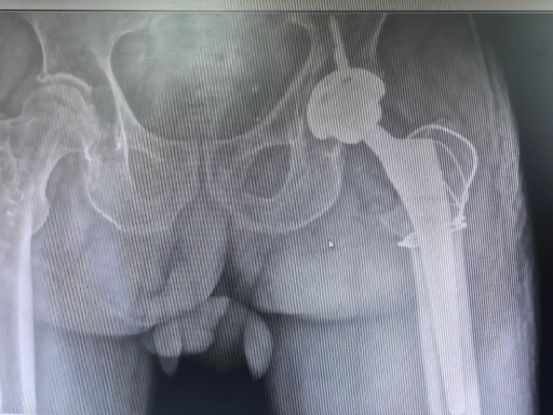

术后摄片